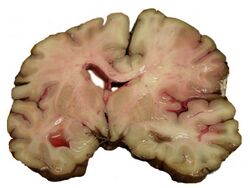

A slice of brain from the autopsy of a person who had an acute middle cerebral artery (MCA) stroke

Stroke can be classified into two major categories: ischemic and hemorrhagic.[19] Ischemic stroke is caused by interruption of the blood supply to the brain, while hemorrhagic stroke results from the rupture of a blood vessel or an abnormal vascular structure. About 87% of stroke is ischemic, with the rest being hemorrhagic. Bleeding can develop inside areas of ischemia, a condition known as "hemorrhagic transformation." It is unknown how many cases of hemorrhagic stroke actually start as ischemic stroke.[2]